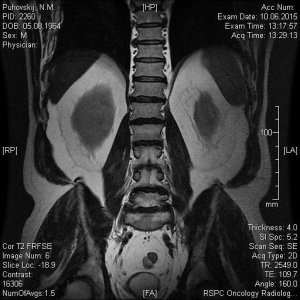

Сегодня сделали МРТ поясничного отдела позвоночника моему отцу. Результат записан на СD диск с множеством фото, заключение, соответственно, прилагается. Но для полной уверенности хотелось бы подтверждения иного специалиста. Основные симптомы: острые и постоянные боли в пояснице, периодически "отказывают" ноги (приходится постоянно менять свое положение-присесть, выгнуться, нагнуться, пройтись и т.п). Не маловажный факт, что около 5 лет назад с идентичными симптомами у папы обнаружили грыжу и удалили ее. Опыт имеется, а страх все равно присудствует. Помогите пожалуйста.

11.jpg48,3 КБ · Просмотры: 707

11.jpg48,3 КБ · Просмотры: 707 -